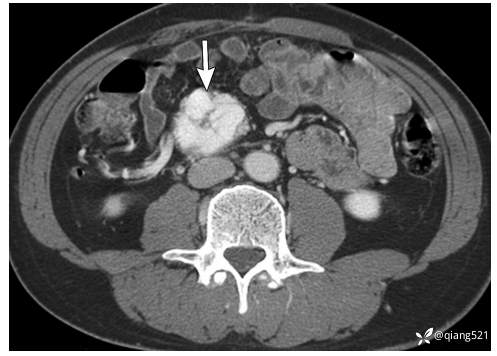

1例21岁男性腹膜圆形细胞瘤。

经下腹部(A)和骨盆(B)的轴位CECT显示腹部和骨盆(箭头)的多灶性不均匀密度软组织肿块。C18-FDG-PET显示腹膜植入物(箭头)和右侧膈下间隙(箭头)摄取FDG。